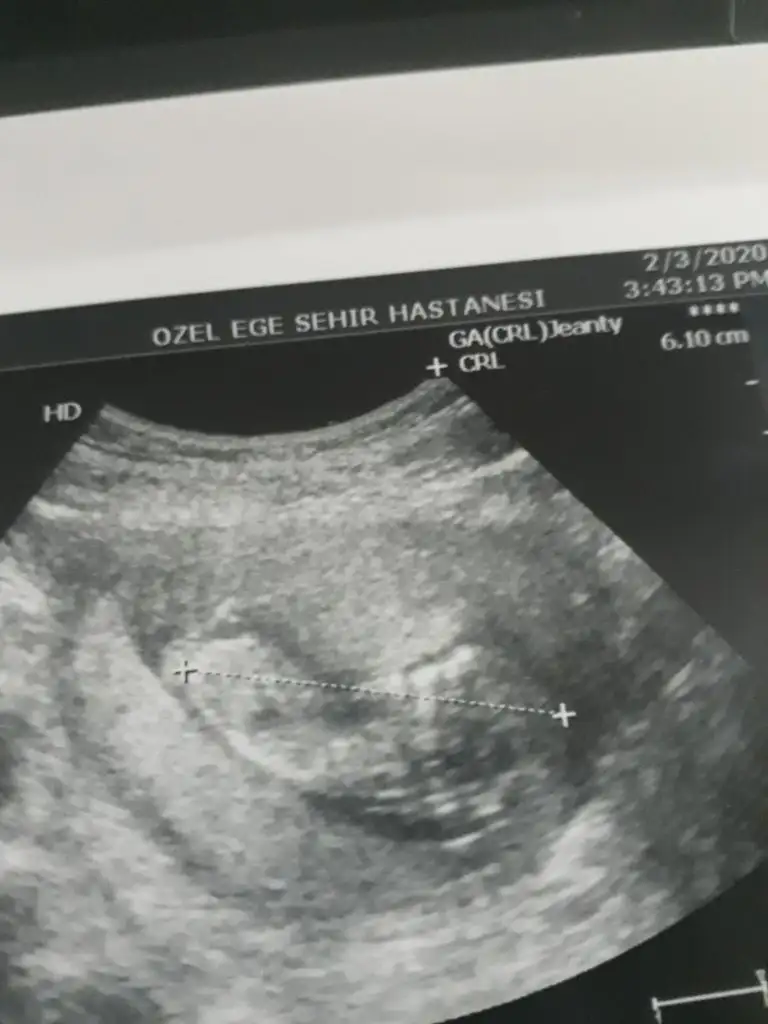

Bu da arkadaşımın bebişinin 12. haftasından görüntüsü. Yine tahmin rica edeceğiz sizden. Sevgiler

Eklentiler

• M 12 hafta.webp

M 12 hafta.webp

10,9 KB · Görüntüleme: 54